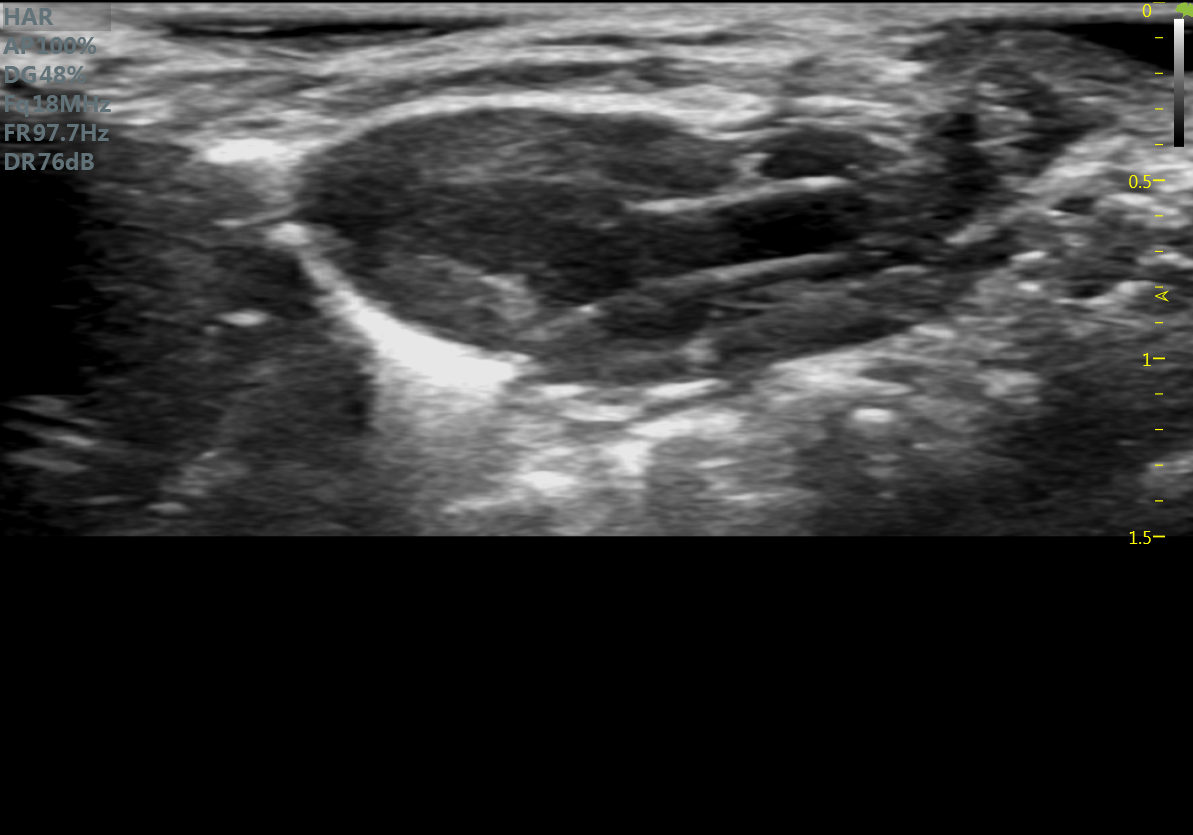

小鼠长轴M型 小鼠短轴M型

小鼠长轴B型 小鼠短轴B型

小鼠主动脉弓 小鼠肾脏血流

小鼠乳头肌水平 小鼠肝脏

大鼠短轴M型 大鼠长轴M型

大鼠长轴B型 大鼠主动脉弓

大鼠胎鼠心脏血流 大鼠心尖四腔

大鼠肝脏 大鼠肾脏